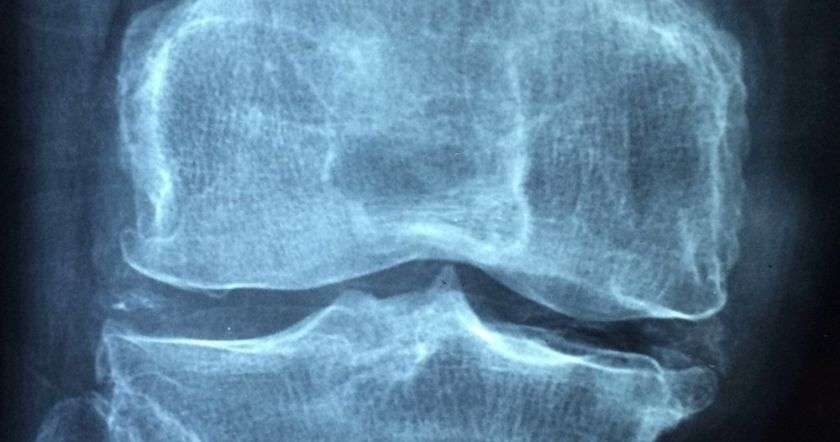

Исследователи из Медицинской школы Стэнфордского университета открыли способ регенерации хрящевой подушки суставов. Для этого сначала нужно нанести небольшое повреждение суставной ткани, а затем использовать химические сигналы для управления ростом скелетных стволовых клеток по мере заживления повреждений. Работа была представлена в журнале Nature Medicine.

В ее основе лежат предыдущие исследования Стэнфордского университета, в результате которых была выделена скелетная стволовая клетка, помогающая в производстве костей, хрящей и особого типа клеток. Чаще всего для лечения повреждений хрящей используется метод микроперелома. Поверхность сустава просверливается, что провоцирует тело создавать новую ткань, похожую на хрящ.